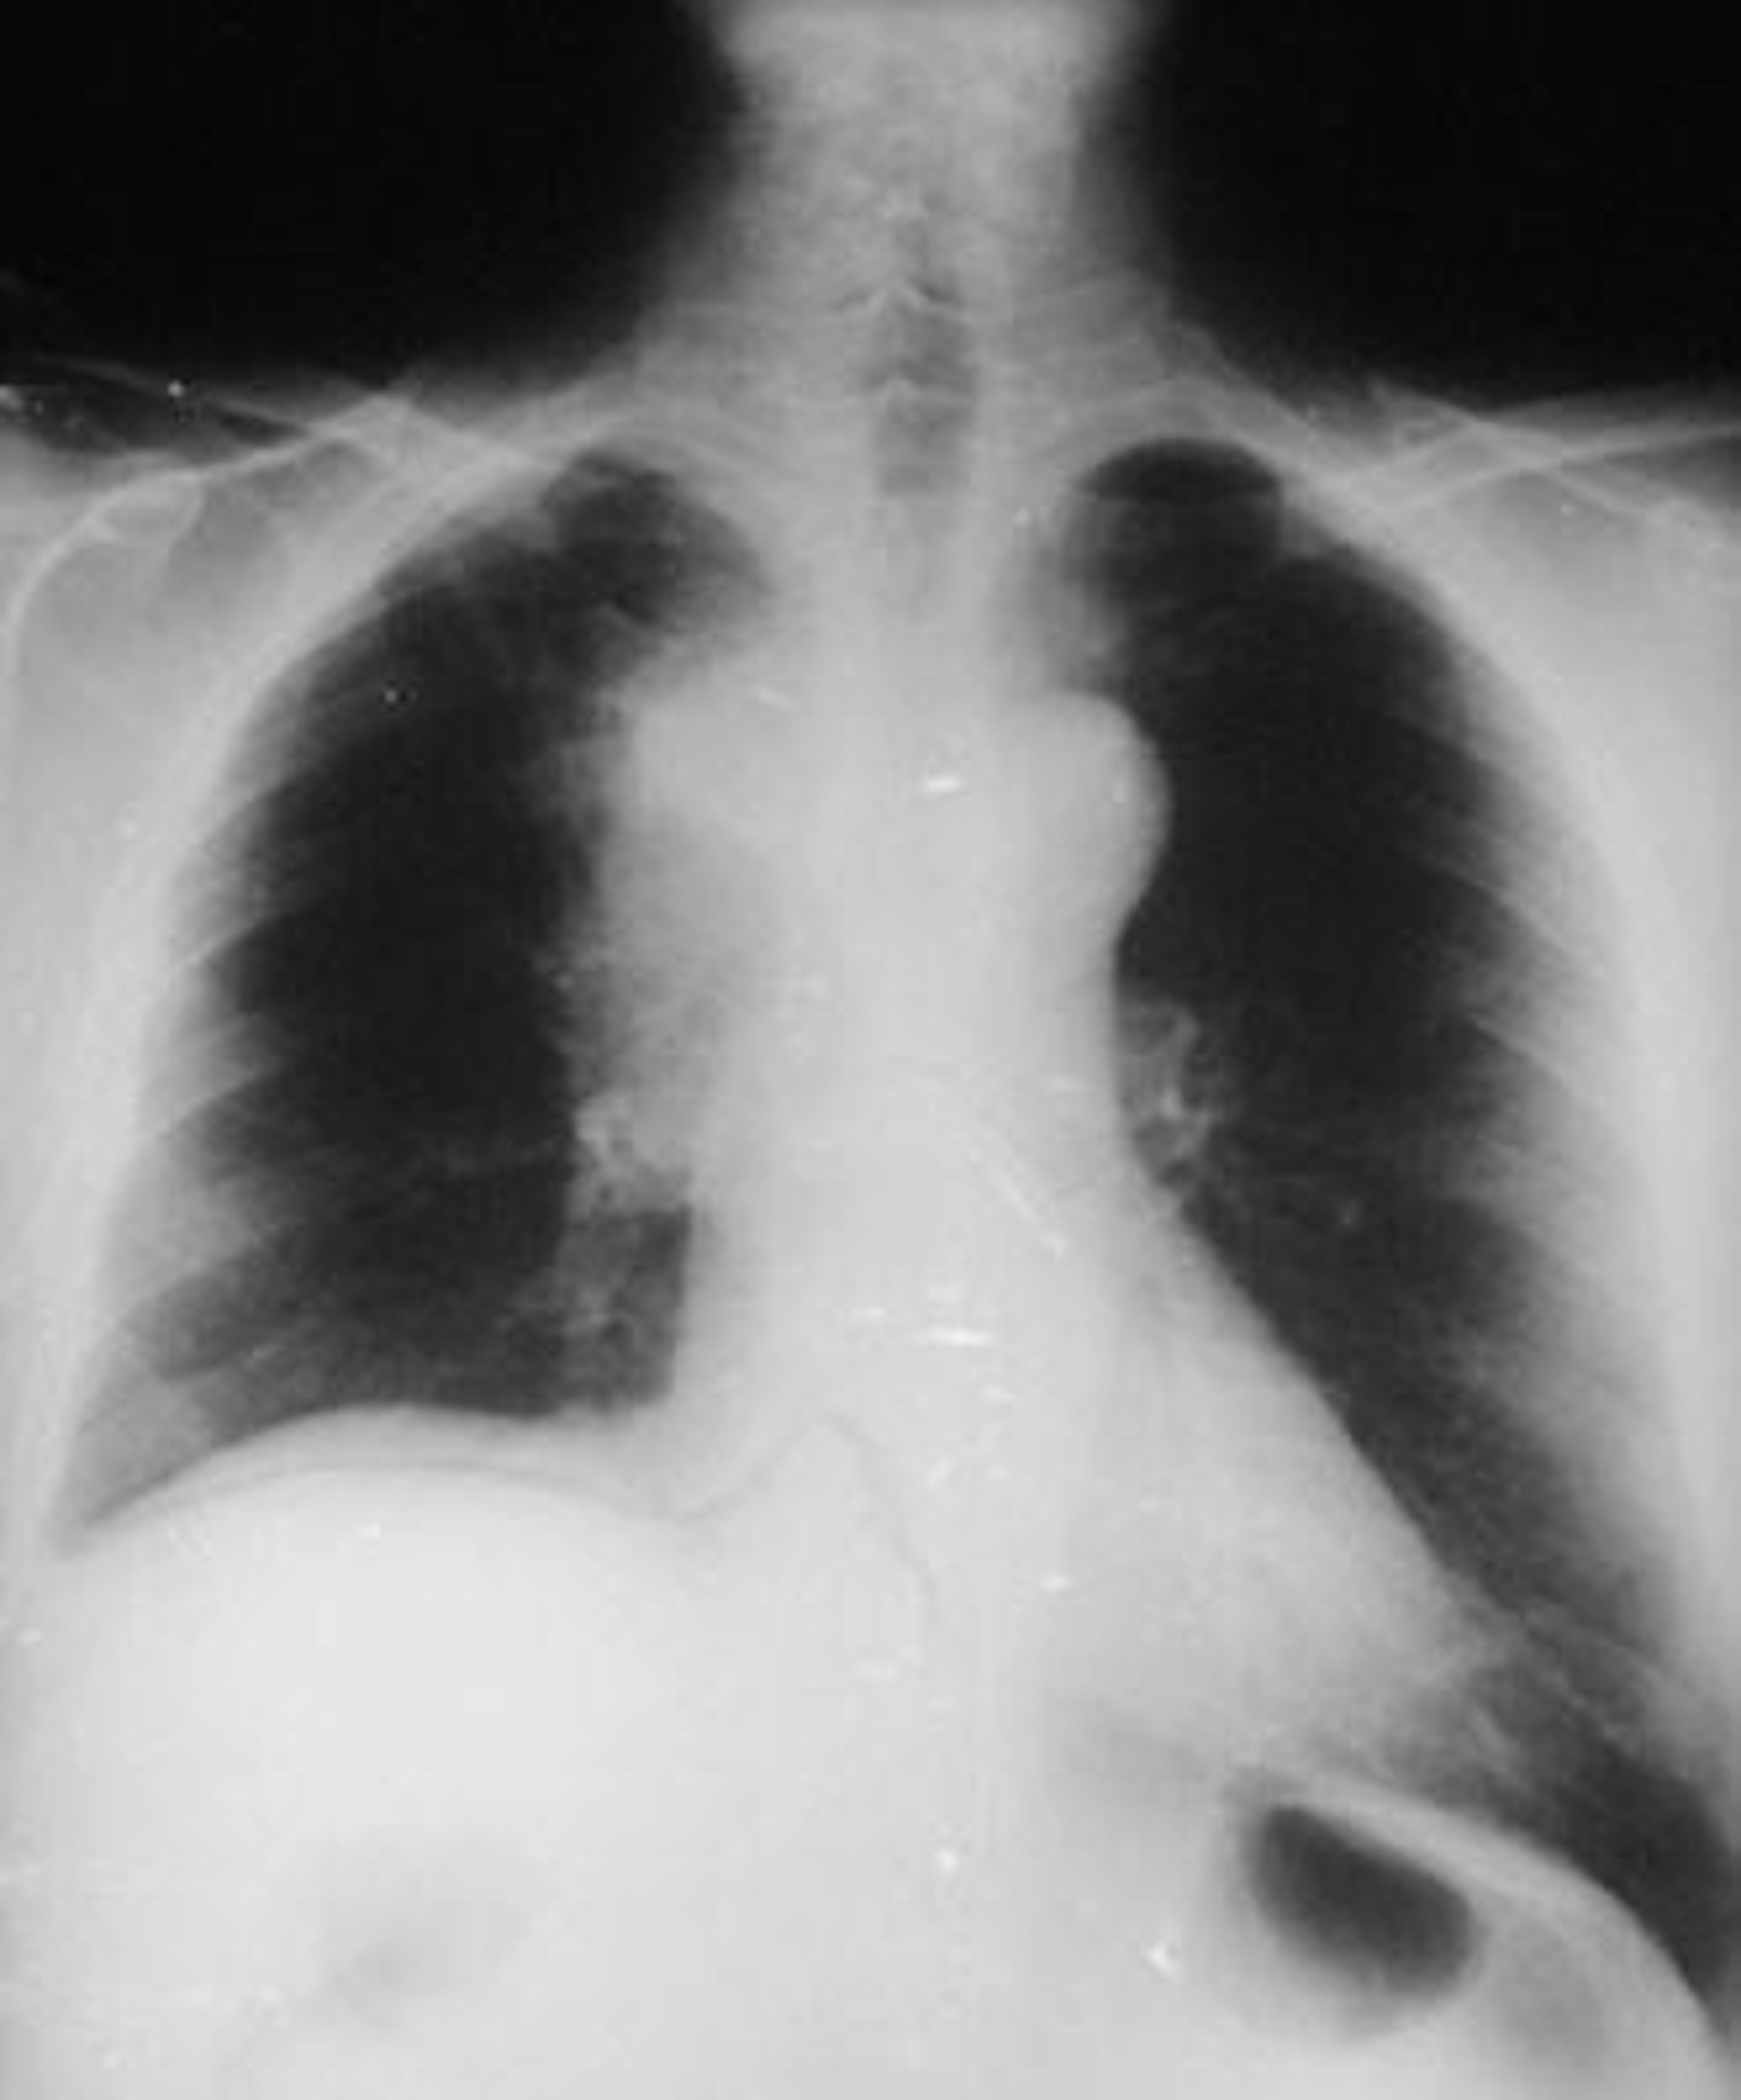

radiografía de pulmón, cáncer